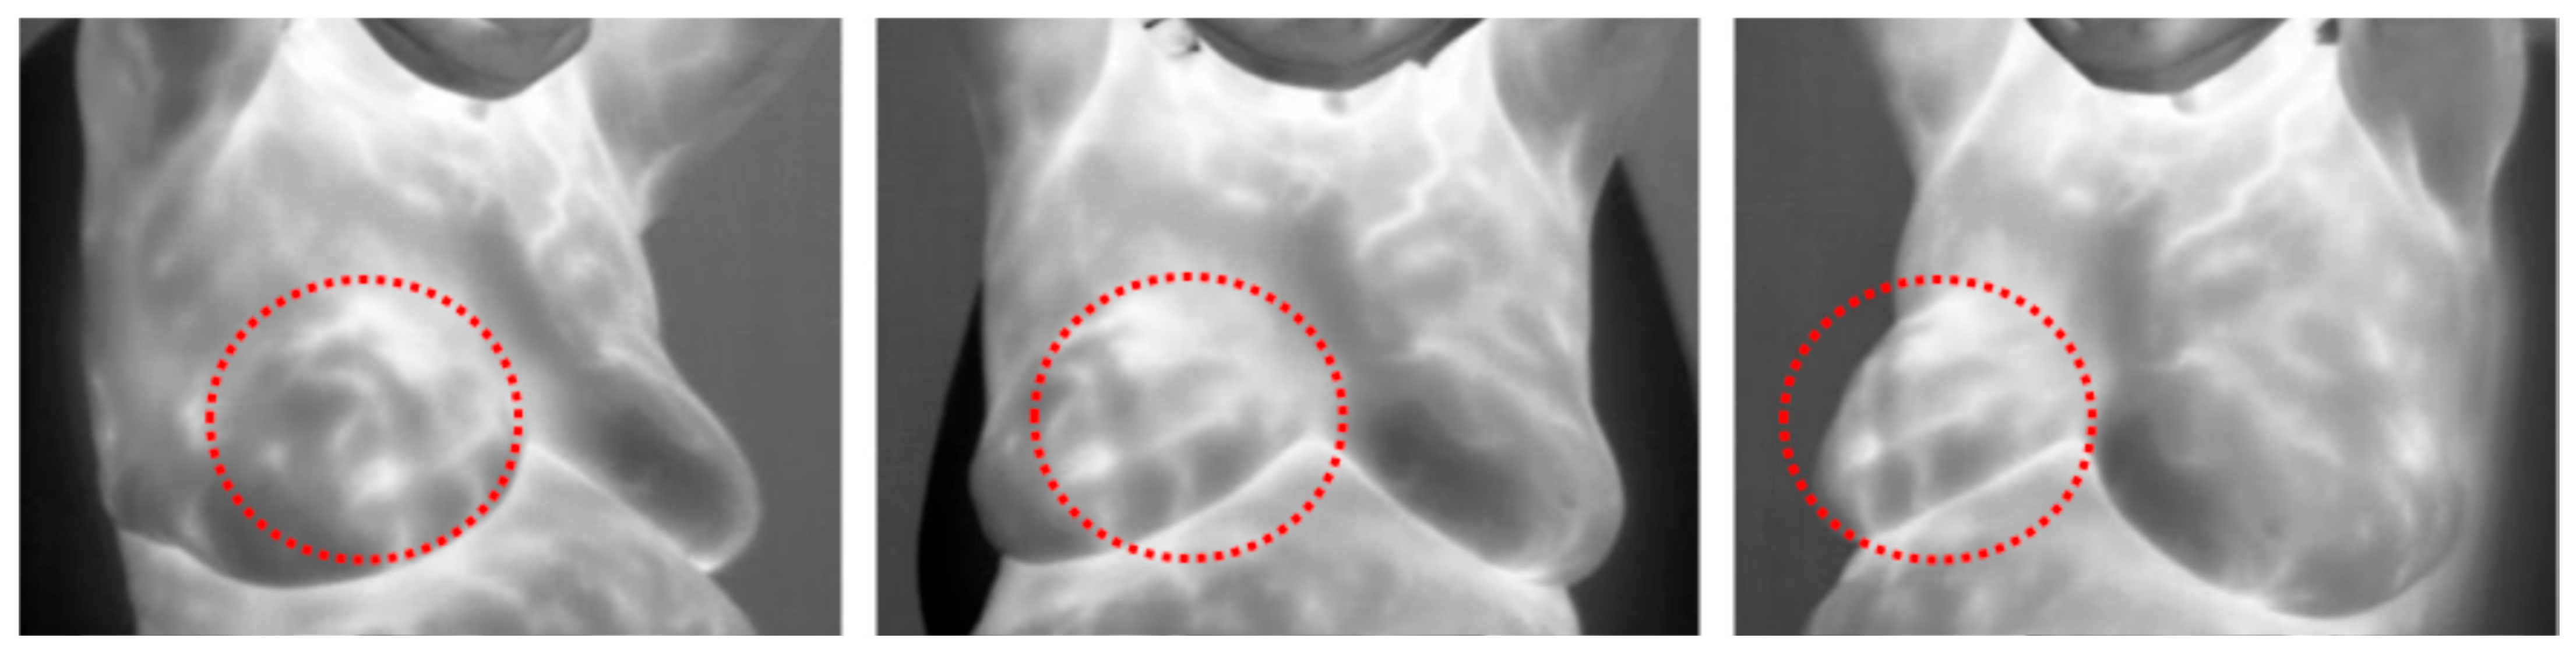

- DMR-IR Dataset: The Database for Mastology Research Infrared (DMR-IR) dataset [39] is the most widely used database in research studies. Of the 26 studies covered in this review, 20, 77%, used this dataset. The DMR-IR dataset includes infrared (IR) images, several digitized mammograms, several ROI masks, and clinical data for 293 patients captured at the Hospital Universitario Antonio Pedro (HUAP) of the Federal University Fluminense. The use of this dataset was approved by the Ethical Committee of the HUAP and registered with the Brazilian Ministry of Health under number CAAE: 01042812.0.0000.5243 and is publicly available at http://visual.ic.uff.br/dmi/, accessed on 6 April 2025. Infrared images are captured using Static Image Thermography (SIT) and Dynamic Image Thermography (DIT) described in [19]. The database also includes segmented images for 56 patients (37 sick and 19 normal). Figure 4 shows sample images from this dataset.